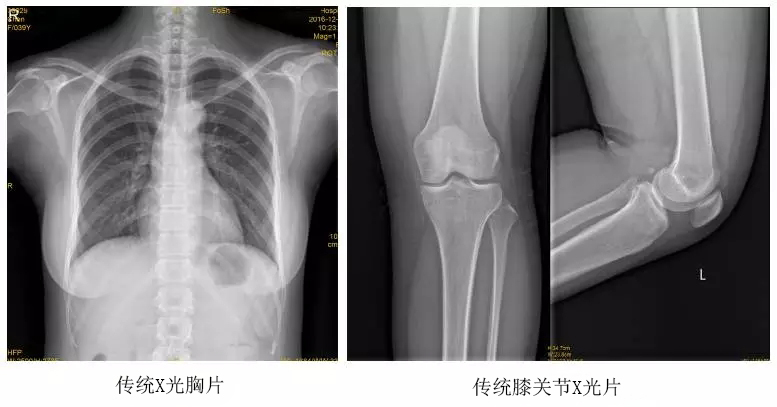

以某院所攝X光片為例,對比傳統攝片與全身拼接功能的區別:

傳統X光片只能觀察每個部位的局部情況,無法在統一體上進行連續、全面的觀察,全脊柱及下肢全長片則能直觀的看到整體形變。通過DR全身拼接功能實現的完整成像,為診治脊柱及下肢畸形提供了完美的臨床影像依據,對臨床診斷、術前手術方案的制定和術后療效的評估等臨床應用具有十分重要的意義,有效滿足了此類疾病臨床診斷和治療的要求。